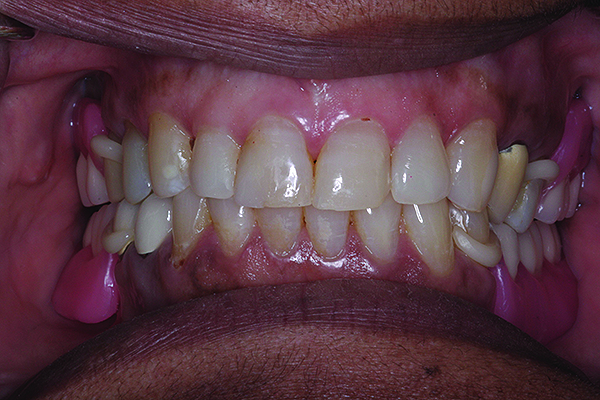

A 65-year-old Caucasian male presented for treatment at the University of North Carolina Dental Faculty Practice. The patient’s chief complaint was the appearance of his teeth, which looked short and had insufficient display when he smiled. The patient was partially edentulous in both the maxillary and mandibular arches and was wearing a cast mandibular RPD and a maxillary interim acrylic RPD. Findings from the clinical and radiographic examinations revealed moderate tooth wear on the posterior teeth and prepared maxillary canines without overlying extracoronal restorations. The prepared teeth were discolored, but no caries was detected clinically when examined using a caries detection solution. Also, the maxillary right first premolar had a coronal fracture and significant tooth wear. The prepared canine teeth were vital with limited interocclusal clearance available for any restorative material at the existing OVD (Figure 14).

Fig 14. Pre-operative condition. Notice prepared maxillary canines with limited interocclusal clearance at existing OVD mainly on the left side.

Figure 14